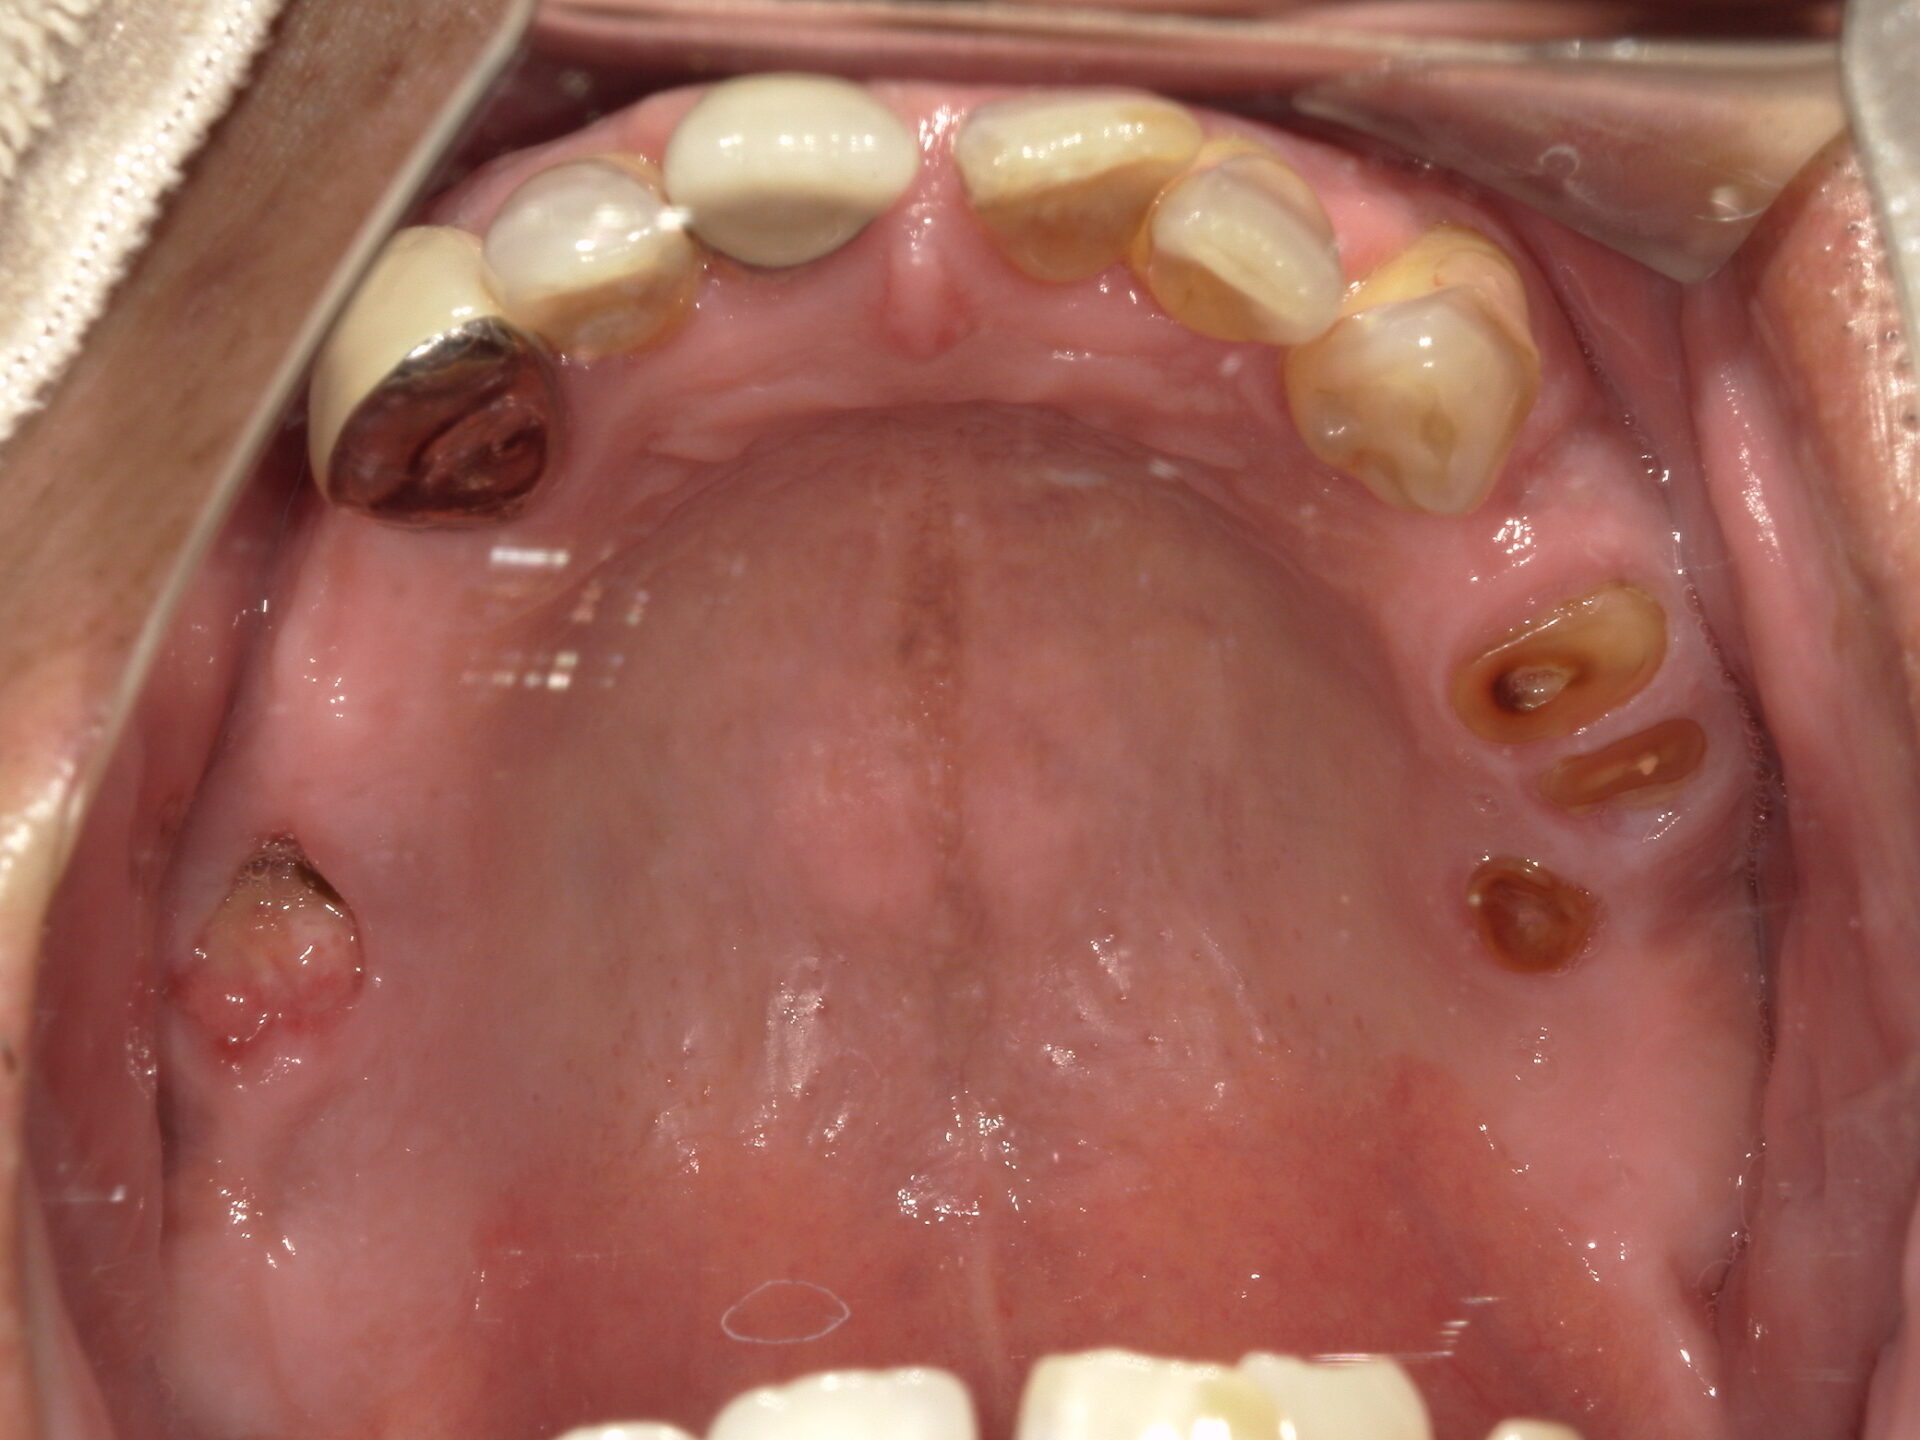

before

after

患者さんの年齢 60代 男性 症状 しっかり噛めるようになりたい 治療内容 インプラント治療(オールオン4) 費用 640万(税抜) 治療期間・回数 治療期間1年半、通院回数12回 デメリット・リスク 骨造成などで費用が増える場合がある 患者さまの声 なんでも噛める。治療して良かった。 - インプラント治療